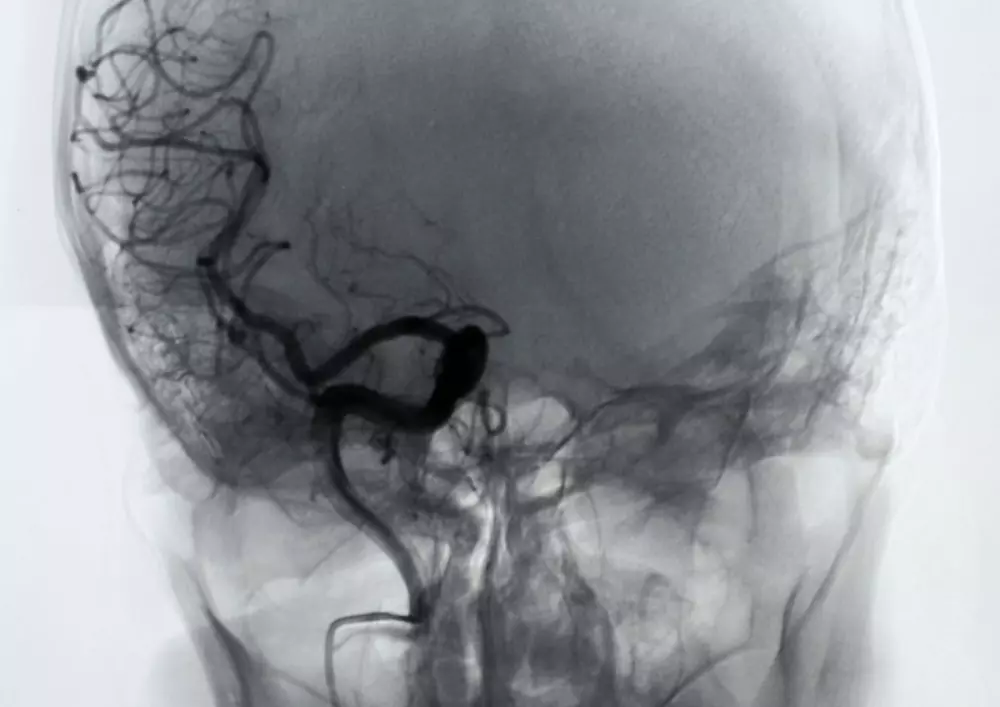

Urazy czaszkowo-mózgoweUrazy czaszkowo-mózgowe wiążą się ze wzrastającą mechanizacją życia i najczęściej dotyczą osób do 30 roku życia. To bardzo poważny problem ze względu na wysoką śmiertelność osób dotkniętych tego typu urazem. Autor wprowadza w tekście rozróżnienie na urazy pierwotne i wtórne, przy czym podkreśla, że rehabilitacja po urazie mózgu pierwotnym jest niezwykle trudna. Wymienia także utrudniające ją czynniki.

Rehabilitacja po urazach czaszkowo-mózgowych powinna przebiegać równolegle z postępowaniem neurochirurgicznym/urazowo-ortopedycznym, by zapobiec uszkodzeniom wtórnym. Ponadto uraz czaszkowo-mózgowy oraz rehabilitacja po urazie mózgu zostają omówione na przykładzie przypadku 19-letniego pacjenta oraz 56-letniego chorego po urazie głowy i towarzyszących urazach wielonarządowych.